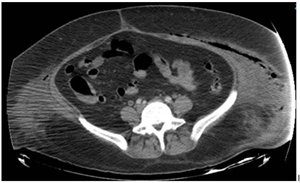

A 43-year-old female with morbid obesity (BMI 42), a history of type 2 diabetes diagnosed 12 years ago without treatment or follow-up, one cesarean section in 2011 and bilateral tubal occlusion in 2018. Who begins with sudden pain in the left inguinal region associated with swelling. She received analgesic treatment without improvement and decided to attend the hospital where is diagnosed with septic shock secondary to soft tissue infection. The results of the blood cytometry were leukocytes 21 000/mm, neutrophils 89%, lymphocytes 6%, hemoglobin 9 mg/dL, hematocrit 28%, and platelets 21 000/mm. Surgical drainage was done and a vulvar abscess was found, dissecting from the mount pubis to the ischiopubic fossa with necrotic tissue and fetid purulent material. During her postoperative period, she continued with purulent secretion outflow; a tomographic study showed the presence of fluid between the subcutaneous cell tissue and the muscular abdominal wall associated with subcutaneous emphysema (Figure 1 & 2). A reintervention was decided for surgical debridement and lavage, among the findings were: labile tissue with fetid necrotic edges, purulent secretion from the left genital area, inguinal region, abdominal subcutaneous cell tissue to the external oblique aponeurosis (Figure 3). In the postoperative period, multiple surgical lavages and debridements were carried out, followed by a VAC system. Nutritional parameters were below the acceptable level, parenteral nutrition was started and enteral nutrition with arginine boluses. A curve of nutritional parameters (albumin, prealbumin, ferritin and transferrin) was made prior to the establishment of the VAC system (Figure 4 & Table 1).

Figure 1 CT scan prior to second intervention that shows subcutaneous emphysema and what it seems and abscess formation.